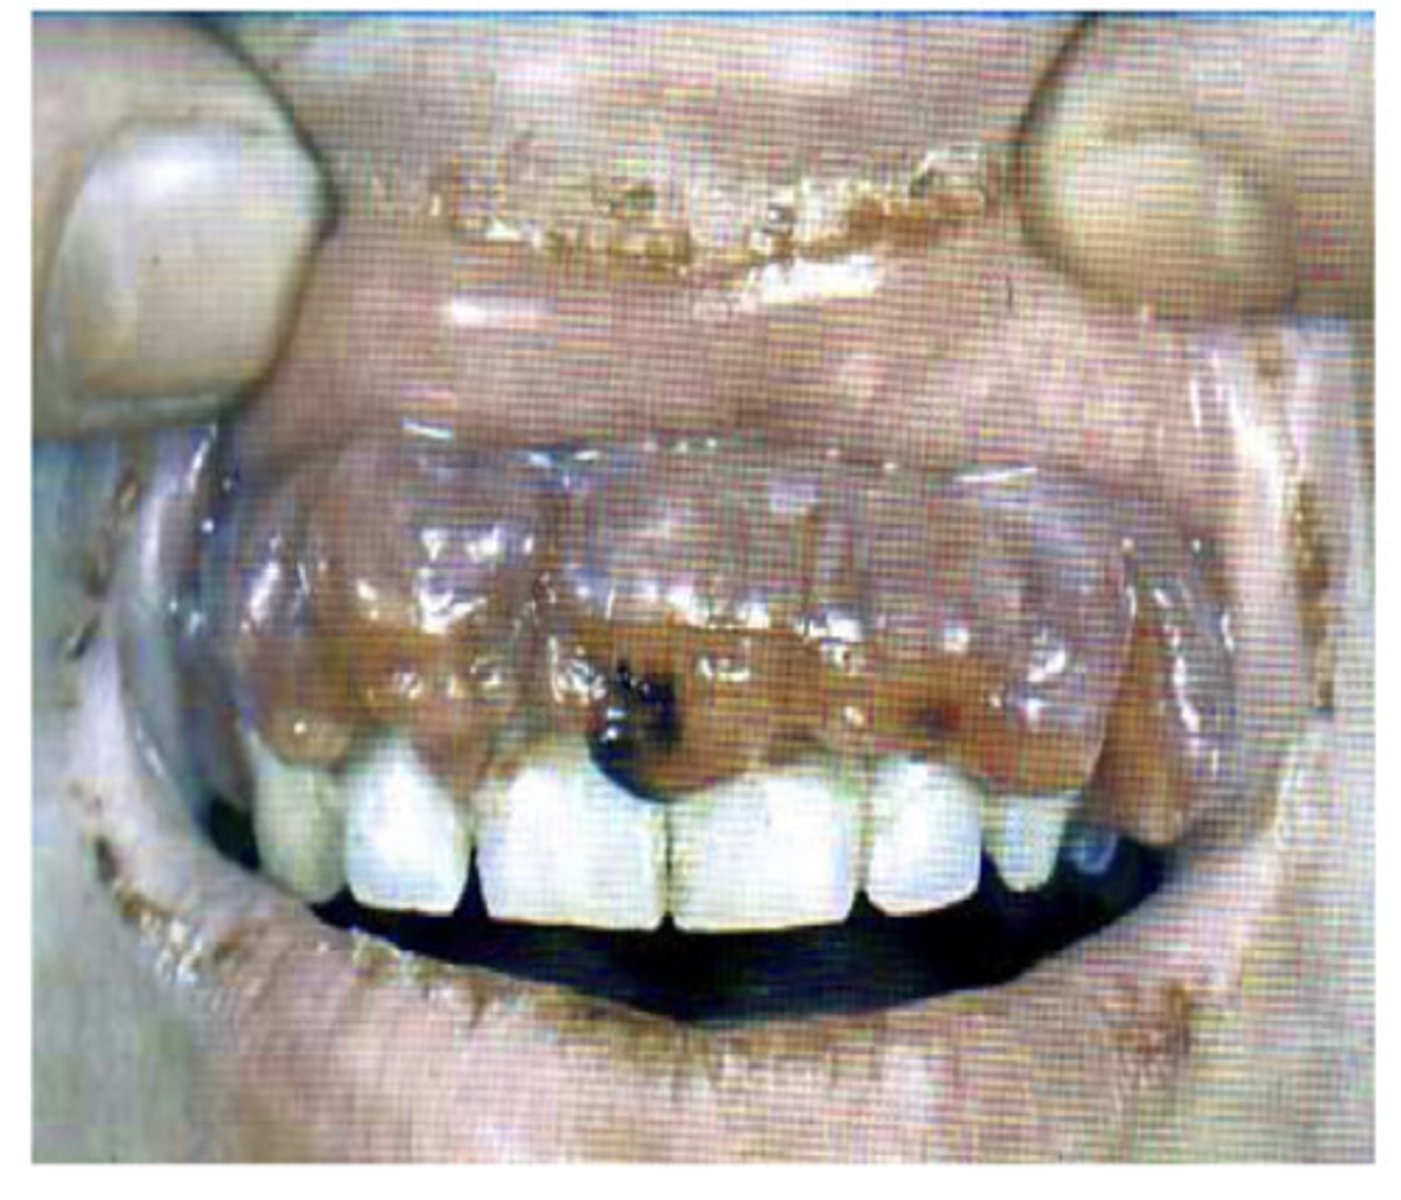

Drug induced gingival hyperplasia

What is this?